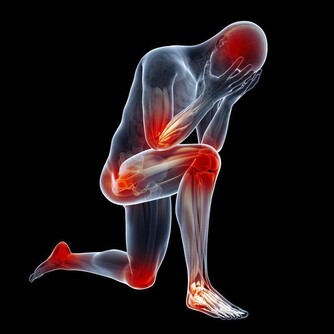

3、腿腳無病痛

如果人過了五十歲以後,腿腳還是沒有一點病痛,行動自如的,那麼說明身體各部位的器官都是正常的,如心臟、大腦、關節、肌肉等都處在正常的狀況下,這時也不會因為身體不適而導致運動量減少,從而可更好的保證身體的健康,正應了那句話“腿好腳好身體好”。